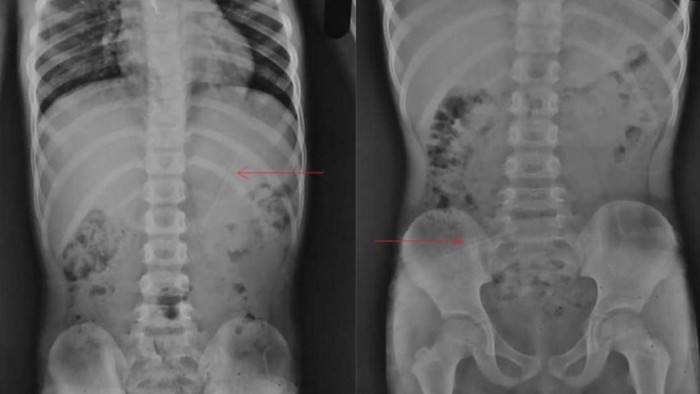

Bocah tersebut kemudian menjalani radiografi pada leher, dada, dan perut. Berdasarkan hasilnya, pensil yang tertelan sepanjang 10 cm itu tertancap di perutnya. Akan tetapi, dokter tidak menemukan efek samping yang buruk terhadap anak tersebut.

"Tidak ada bukti komplikasi yang tercatat, dan panjang pensil diperkirakan sekitar 10 cm, mengingat panjangnya pada radiografi dan skala pada mesin sinar-X," kata dokter dikutip dari jurnal tersebut.

Setelahnya, bocah tersebut menjalani pemindaian kedua yang menunjukkan pensil itu berada di dekat persimpangan ileocecal, katup otot yang memisahkan usus kecil dan usus besar.